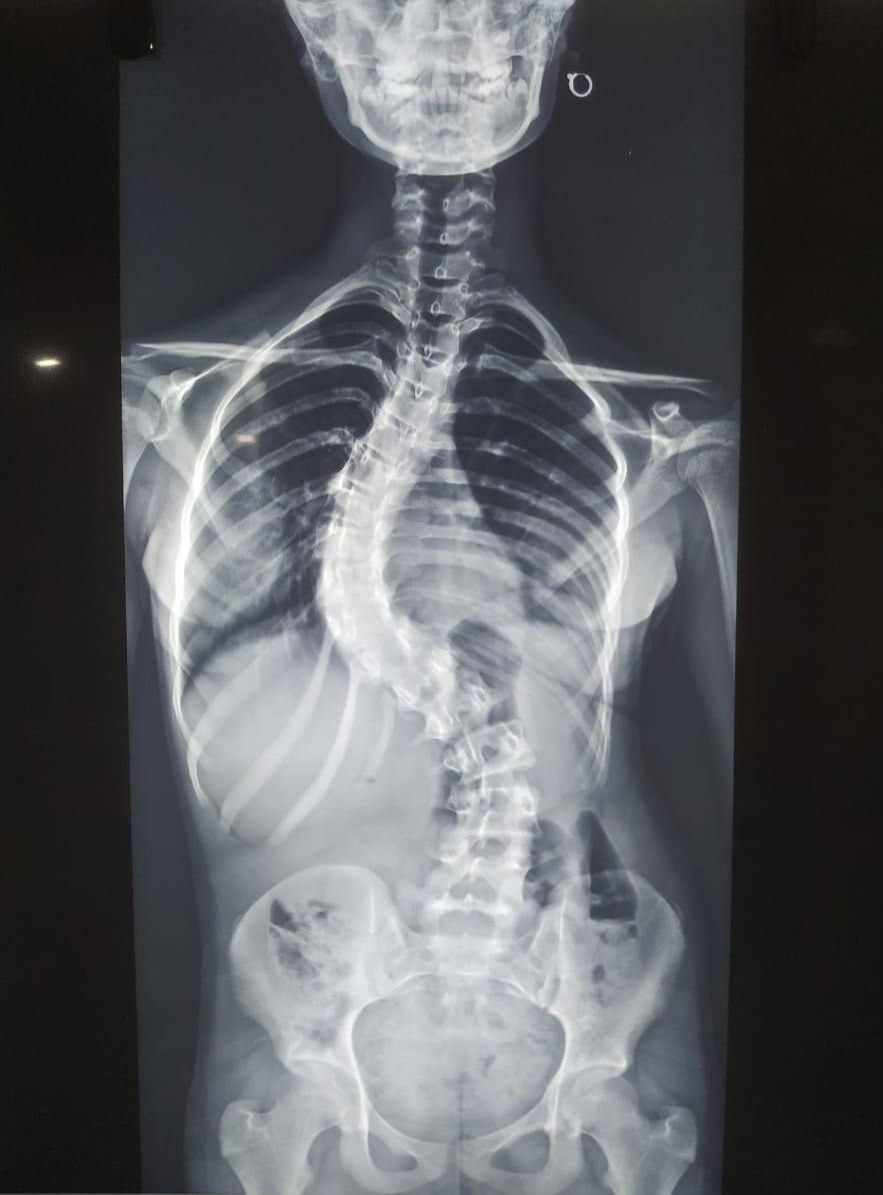

Preoperative standing X-rays of the spine revealed a severe double major curve: a large right thoracic curve and a compensatory left lumbar curve, both exceeding the threshold that necessitates surgical intervention. The severity of these curves posed risks of progression, cosmetic disfigurement, and potential compromise of pulmonary function in the future. The overall spinal balance was poor, with one shoulder higher than the other and a tilted pelvis, which further emphasized the deformity. Given the extent of the curvature, posterior spinal instrumentation with fusion was indicated in order to restore alignment, achieve curve control, and prevent further worsening of the deformity.